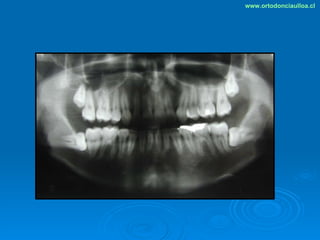

Este documento presenta dos casos clínicos de pacientes que recibieron tratamiento de ortodoncia. El primer caso fue de una paciente femenina de 14 años con apiñamiento dental y mordida cruzada que fue tratada mediante extracción de premolares y alineamiento dental. El segundo caso fue de un paciente masculino de 14 años con clase II esqueletal y desarmonía dentomaxilar que fue tratado con extracción de premolares y corrección de mordida. Ambos casos mostraron mejoría después de 3 años de tratamiento.